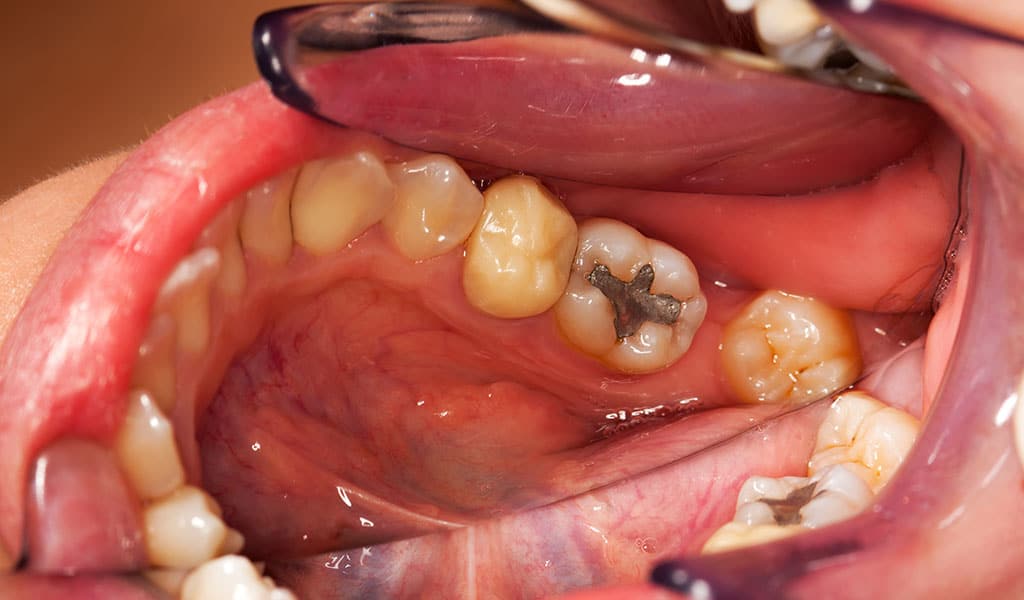

The Journal of Dentistry has recently published a study revealing that fillings could do more harm than good, potentially damaging surrounding teeth.

The researchers discovered that after five years, that six out of ten teeth that sat beside a filling were decaying. Experts have suggested that the secondary decay is due to the trauma of the original filling.

Further issues surrounding the provision of fillings arose from this study when it was found that particular dentists had a correlating commonality in patients who developed further decay.

“Once a dentist has gone into a tooth, they may accidentally damage another tooth. Dentists need to keep up to date with the latest techniques to ensure they don’t damage other teeth when they do a filling,” explained Birmingham University’s dental expert Professor Walmsley.

The study’s lead researcher, Simen Kopperud from the Nordic Institute of Dental Materials, Oslo, explained that filings were not a complete answer to the issue of decay. “The most important message is that if restoration takes place in one place the problem of decay is not solved. It is highly possible that the intervention by the dentist causes a problem in adjacent teeth. Fillings are not an ideal solution but at the moment it’s the best solution we have.”